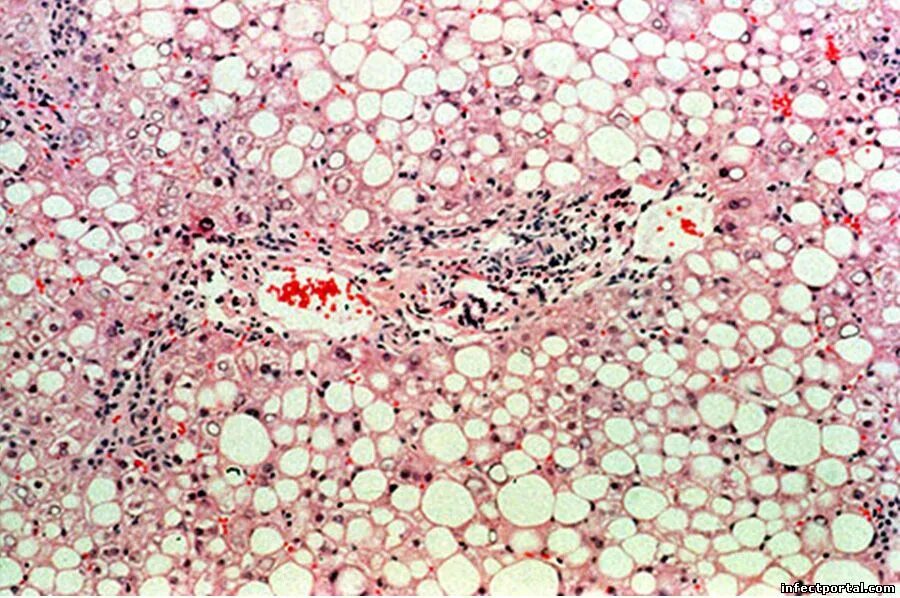

Диффузные изменения поджелудочной железы стеатоз